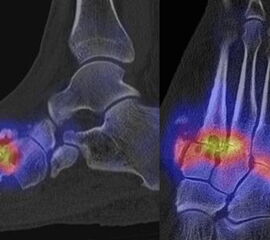

In Abbildung 3.4. ist ein typisches Beispiel für ein symptomatisches Os trigonum dargestellt.

Bei der Differenzialdiagnose von Impingement-Syndromen am Sprunggelenk kann das SPECT/CT den Ort der Symptome- verursachenden Stressreaktion darstellen 32. Eine typische Ursache für ein posteriores Impingement kann ein Os trigonum sein. Scherkräfte im Bereich der Synchondrose eines Os trigonum lösen hypermetabole Stressreaktionen aus. Die Exzision des Os trigonum stellt eine erfolgreiche Therapie dar, sodass der Befund eines szintigraphisch aktivierten Os trigonum den Erfolg einer chirurgischen Therapie vorhersagen kann 3334.